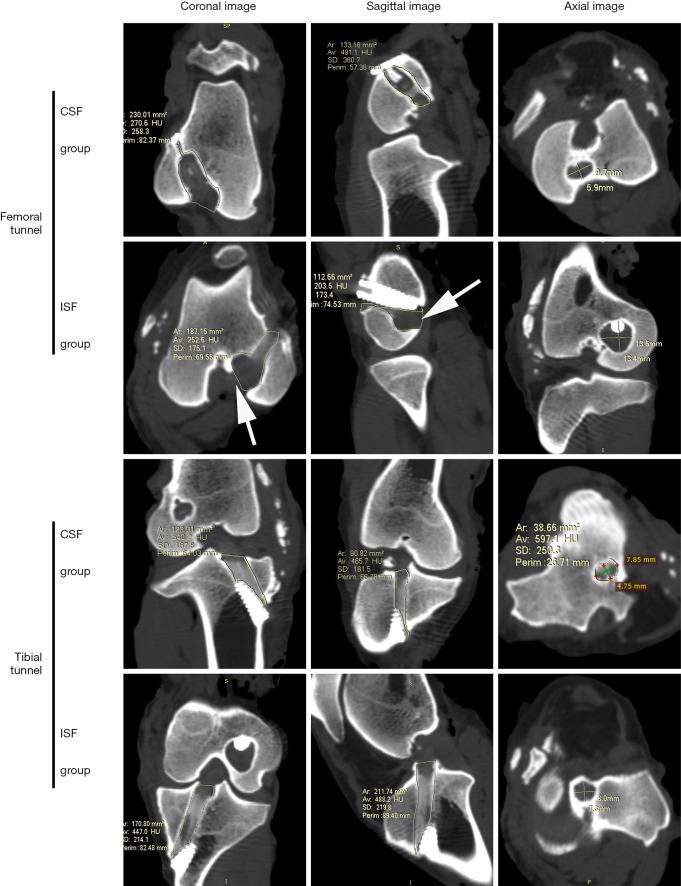

Forty sheep underwent ACL reconstruction of the right knee with PET artificial ligament. The graft was fixed with ISF or CSF for femoral fixation. Animals were randomly assigned to the ISF (n=20) or the CSF (n=20) groups. The sheep were sacrificed at 3 or 12 months postoperatively for biomechanical tests, micro computed tomography (micro-CT) scans, and histological assessments.

The mean load-to-failure between the CSF group (836±355 N) appeared higher than that of the ISF group (604±277 N) at 3 months, but no significant difference was detected between the groups (P=0.24). At 12 months, there was also no significant difference in load-to-failure between the CSF and ISF groups (1,194±350 1,097±764 N; P=0.78). According to the micro-CT scan results, the femoral bone tunnel diameter of the ISF group appeared larger than that of the CSF group at 3 months (12±1 10±1 mm; P=0.02) and similar to that of the CSF group at 12 months (12±1 11±2 mm; P=0.38). Furthermore, histological results showed that at the graft-tunnel interface of the femoral tunnel aperture, disoriented fibers formed in the ISF group while oriented and dense fibers formed in the CSF group.

ACLR with synthetic ligament by cortical suspension devices with adjustable loops demonstrated a better graft-bone healing capacity at the femoral tunnel aperture compared with that from titanium interference screws over 12 months postoperatively. No significant difference was found in biomechanical strength between the two fixation methods during the early healing stage.

在3个月时,CSF组的平均失效载荷(836±355 N)似乎高于ISF组(604±277 N),但两组之间未检测到显著差异(P = 0.24)。在12个月时,CSF组和ISF组之间的失效载荷也没有显著差异(1,194±350对1,097±764 N;P = 0.78)。根据micro-CT扫描结果,ISF组在3个月时股骨骨隧道直径似乎大于CSF组(12±1对10±1 mm;P = 0.02),在12个月时与CSF组相似(12±1对11±2 mm;P = 0.38)。此外,组织学结果显示,在股骨隧道开口处的移植物-隧道界面,ISF组形成了排列紊乱的纤维,而CSF组形成了排列有序且致密的纤维。

与钛合金干涉螺钉相比,术后12个月内,采用带有可调节环的皮质悬吊装置进行合成韧带ACL重建在股骨隧道开口处显示出更好的移植物-骨愈合能力。在早期愈合阶段,两种固定方法的生物力学强度没有显著差异。